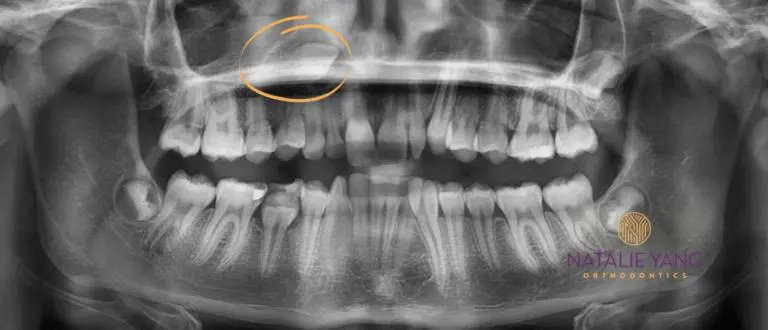

We can spot problems early

In addition to underbites, big overbites, and crossbites, we can also spot problems with the adult teeth inside the jaw bones.

Some common things we look for are:

1. Missing adult teeth – (even with the baby tooth still in place).

2. Adult tooth growing in the wrong direction

3. Adult teeth that are too big for the mouth

4. Adult teeth that are stuck behind other teeth (usually due to overcrowding)

Knowing about these issues early will help you to plan for the future. Sometimes Phase I is necessary for intervention.